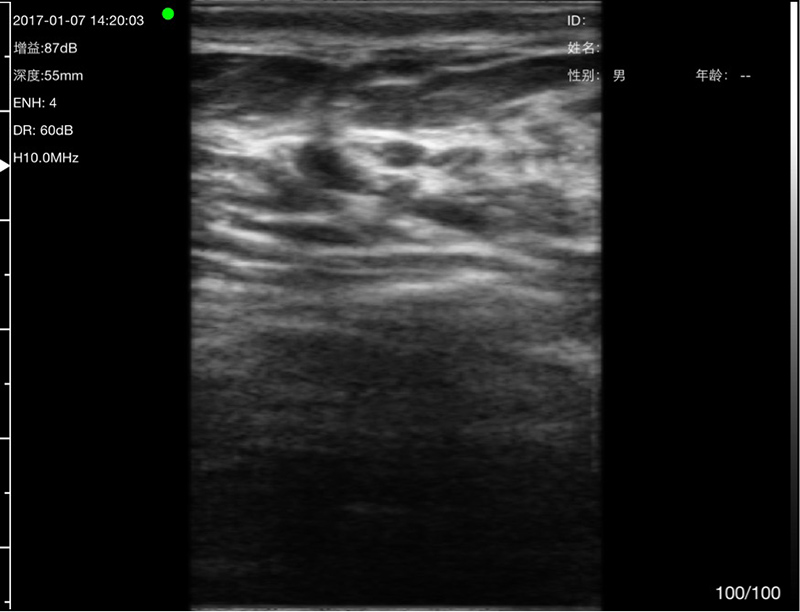

• Scan mode: Electronic Array, convex with cardiac namely phased array or linear array scanning;

• Frequency: Micro-Convex probe 5.0/7.0MHz, Linear probe 10/12MHz

• Scanning Depth: Micro-Convex 60-160mm, Linear 20-80mm, adjustable